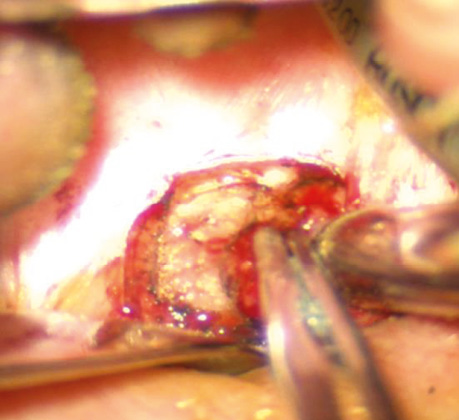

Пацієнт В., 40 років. Встановлено діагноз — плоскоклітинна карцинома м’якого піднебіння T2N0M0. Проведено трансоральну CO₂-лазерну резекцію м’якого піднебіння. Етапи хірургічного втручання представлені на рис. 1–2.

Рис. 2. Вид операційної рани після виконаної трансоральної CO₂-лазерної резекції м’якого піднебіння